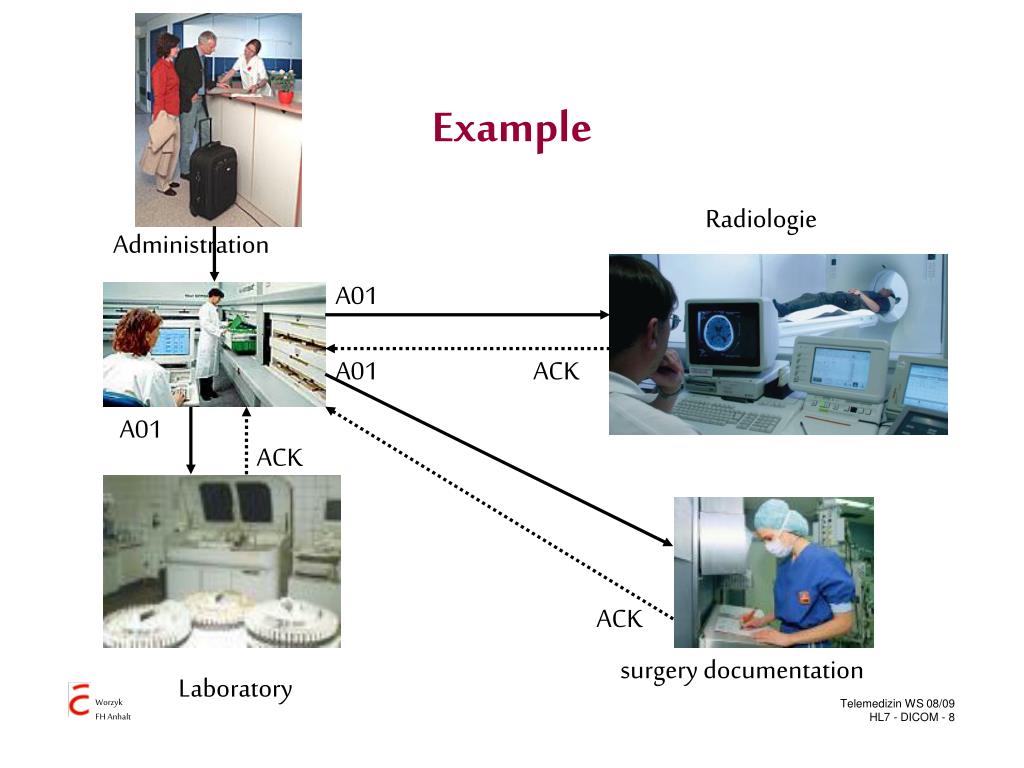

Лазерная камера для печати медицинских изображений на пленке стандарт dicom